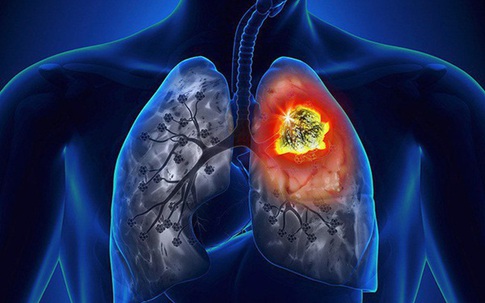

Ung thư phổi đang hàng ngày cướp đi sinh mạng của con người, rất nhiều người không biết rằng chính những thói quen tưởng chừng vô hại như nấu nướng trong nhà bếp lại là “kẻ sát nhân” đang hủy hoại sức khỏe của con người.

Môi trường sống ô nhiễm cũng là một trong những nguyên nhân lớn gây hại sức khỏe. Đây là các giải pháp đơn giản để ngăn ngừa ung thư phổi. Mỗi người đều nên tham khảo áp dụng.

Trong 10 loại ung thư phổ biến thường gặp tại nước ta thì ung thư phổi xếp thứ nhất và là nguyên nhân gây tử vong hàng đầu. Vì thế, việc nhận biết những dấu hiệu ban đầu của căn bệnh ung thư phổi là vô cùng quan trọng.

Ung thư phổi là loại ung thư phổ biến nhất và cũng là ung thư gây tỷ lệ tử vong cao nhất trên toàn thế giới. Tại Mỹ mỗi năm có khoảng 174.000 người mắc mới và 160.000 người tử vong.